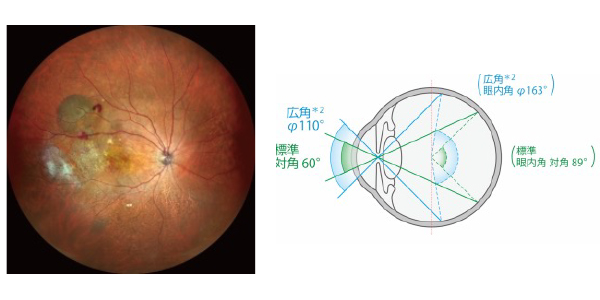

ミランテ

特長

・眼底マルチモダルイメージング

・4Kの高解像度な広角*1・カラーSLO

・16.5×12mmの広範囲OCT撮影

・長眼軸長正常眼データベース*1を搭載可能

・OCT-Angiography*1による診断サポート

・Bスキャンデノイジングソフトウェア*1を搭載可能

当院ではニデック社の最上位機種であるミランテを導入しております。ミランテは従来の眼底カメラに比べてかなり眼底の広い範囲を撮影可能であり、電子カルテと組み合わせることにより、今までは眼科医しか見れていなかった眼底の端の病変も患者様に診察室で見て頂くことが可能です。

またこの器械一台で、広角カメラ、OCT,OCTアンギオ、FAG、の検査が出来る優れものです。

検査の時に場所を移動する必要は無く、またOCTアンギオは点滴注射をして、今までのFAG検査で必要だった造影剤を体内に入れる負担のある検査が必要なくなりました。そのため、糖尿病網膜症や網膜中心静脈分岐閉塞症における無灌流領域の場所がすぐに分かり、治療につなげることができます。

もちろんOCT(網膜の断層図)もとてもきれいに撮影できます。